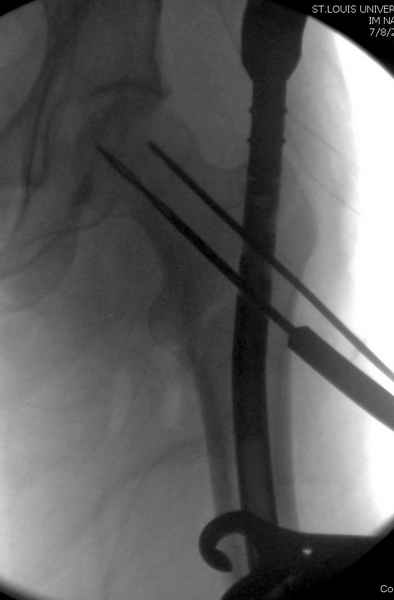

Второй случай тоже репозиция из малого доступа, больному 19 лет, множественные огнестрельные повреждениия конечностей, живота и черепа, правая конечность холодная, без пульсации. Ортопедический диагноз: огнестрельный перелом правого бедра. При срочной ангиографии повреждения сосудов не подтвердилось, конечность из-за ургентности состояния больного зафиксирована временным наружным фиксатором и больной оставлен на операционном столе для срочной лапаротомии хирургической службой.

Больной долго оставался нестабильным, только на 14 день удалось заменить на антеградный интромедуллярный штифт TFN (trochanteric femoral nail) SmithNephew. После неудачной попытки закрытой репозиции, несмотря на использование "joystick", проксимальный стержень от

наружного фиксатора, (перелом начал срастаться) репозицию провели из малого доступа, затем остальные этапы операции.

Случай был представлен из-за того, что больного оперировали после наружной фиксации и был риск инфекцирования через места проведения стержней (на снимках), прошло больше 3 месяцев, выписан из амбулаторной службы из-за отсутсвия надобности дальнейшего наблюдения.